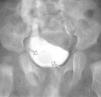

Objetivo: Ilustrar el espectro de hallazgos radiológicos de las duplicaciones del tracto urinario y mostrar la eficacia de los ultrasonidos, la cistouretrografía miccional seriada (CUMS), la urografía intravenosa (UIV), el estudio isotópico y la resonancia magnética (RM) en el manejo de estas entidades. Material y métodos: Hemos revisado retrospectivamente los hallazgos radiológicos de las duplicaciones del riñón, uréter, vejiga y uretra a partir de los datos de nuestro archivo de patología genitourinaria pediátrica. Todos los casos cuentan con estudio ecográfico, mientras que la CUMS, la UIV, el estudio isotópico y la RM se realizaron en función del tipo de duplicación. Hacemos hincapié en las bases embriológicas de los hallazgos radiológicos que, cuando fue posible, se cotejaron con los hallazgos anatomopatológicos. Resultados: Las duplicaciones completas o incompletas afectaron con más frecuencia al sistema pielocalicial y al uréter (pelvis renal bífida, uréter semibífido, uréter bífido bajo, duplicación ureteral completa y triplicación). Las duplicaciones vesicales se muestran en los planos sagital y coronal, aunque la forma más frecuente fue la división sagital con dos vejigas resultantes contiguas separadas por un pliegue peritoneal con tejido areolar fino. Las duplicaciones uretrales o las uretras accesorias se dieron fundamentalmente en el plano coronal; sin embargo, también describimos la duplicación en el plano sagital en ausencia de duplicación vesical. Mostramos un caso extremadamente raro de duplicación completa de uretra femenina. Conclusión: Mostramos una visión de conjunto de las duplicaciones del tracto urinario y discutimos la utilidad de varias técnicas de imagen disponibles. Dado que estas entidades tienen una apariencia radiológica característica, este artículo puede ser útil para comprender mejor estas anomalías.

Objective: To illustrate the spectrum of imaging findings for urinary tract duplications and to show the efficacy of ultrasonography (US), voiding cystourethrography (VCU), intravenous urography (IVU), scintigraphy, and magnetic resonance (MR) in the management of these entities. Material and methods: We have reviewed the imaging findings for cases of renal, ureteral, vesical, and/or urethral duplication from our pediatric genitourinary pathology archive. All patients underwent US examination; VCU, IVU, scintigraphy, and MR studies were performed in function of the type of duplication. We explain our findings within the framework of embryological development and correlate the imaging findings with the histopathologic findings whenever possible. Results: Complete or partial duplications most commonly affected the pyelocalyceal system or the ureters (bifid renal pelvis, bifid mid-ureter, low bifid ureter, complete ureteral duplication and triplication). Vesical duplications are shown in the sagittal and coronal planes, although the most common presentation was sagittal division resulting in two contiguous bladders separated by a peritoneal fold with thin areolar tissue. Ureteral duplication or accessory ureters were mostly seen in the coronal plane; however, we also describe duplication in the sagittal plane in the absence of vesical duplication. We show an extremely rare case of complete duplication of the female urethra. Conclusion: We provide an overview of the set of urinary tract duplications and discuss the usefulness of the different imaging techniques available for each type. As these entities have a typical radiological appearance, this article can help to understand these anomalies better.